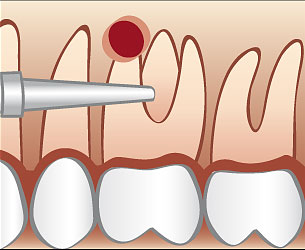

Ablauf einer Wurzelspitzenresektion

Üblicherweise wird eine Wurzelspitzenresektion in örtlicher Betäubung durchgeführt. Die Schleimhaut wird vom Knochen abgelöst und die Wurzelspitze mit Hilfe eines Spezialbohrers freigelegt. Anschließend wird die Wurzelspitze abgetragen und der Entzündungsherd oder eine eventuell vorhandene Zyste entfernt. Eine antimikobielle photodynamische Therapie mittels Softlaser kann für eine zusätzliche Keimreduktion sorgen. Bei Bedarf werden die dünnen Kanäle im Bereich der Wurzelspitze mit speziellen Ultraschallgeräten erweitert mit einem speziellen Füllungszement abgedichtet. Danach wird dessen Dichtheit überprüft und die Schleimhaut vernäht.